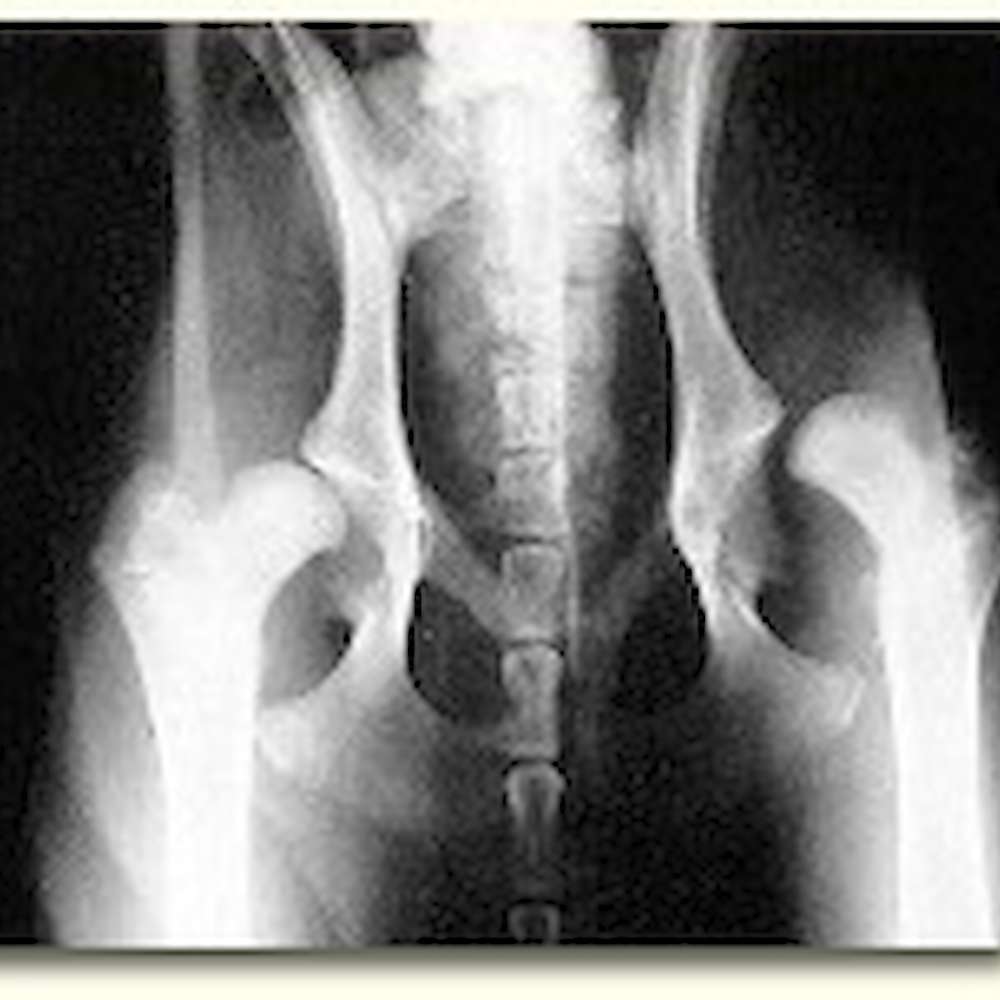

It is especially important to perform a Distraction Index (DI) on dogs that have normal appearing hips on the ventrodorsal extended view, such as appears to be the case in the image on the right. Dogs that are diagnosed as having excellent hips on the traditional VD view can actually have a huge amount of laxity. PennHIP's recommendation is to limit breeding to those dogs that have normal appearing hips on the VD hip extended view and that also have a DI at the breed's mean laxity or tighter.

Luxation means dislocation. A luxated hip is one that has extreme laxity such that it displays dislocation of the two bones of the joint. The x-ray image at the top right of this page demonstrates a fully luxated hip on the right side of the image.

Subluxation means a partial dislocation of two joint members. The x-ray image at the top right of this page demonstrates a subluxated hip on the left side of the image.